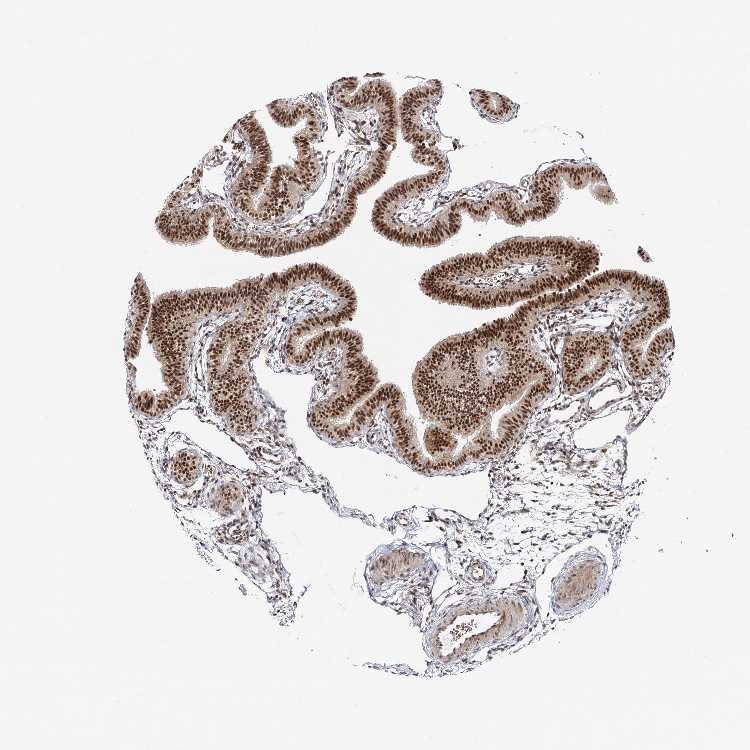

TISSUE PRIMARY DATA FALLOPIAN TUBE Show tissue menu

FALLOPIAN TUBE - Antibody stainingi

Antibody staining in the annotated cell types in the current human tissue is reported as not detected, low, medium, or high, based on conventional immunohistochemistry profiling in selected tissues. This score is based on the combination of the staining intensity and fraction of stained cells.

Each image is clickable and will lead to virtual microscopy that enables deeper exploration of all samples and also displays staining intensity scores, fraction scores and subcellular localization as well as patient and tissue information for each sample.

Antibody HPA038340Antibody HPA038341

Ciliated cells (cell body) -High

Ciliated cells (cilia axoneme) -Not detected

Ciliated cells (ciliary rootlets) -Low

Ciliated cells (tip of cilia) -Not detected

Glandular cells High-

Non-ciliated cells -High